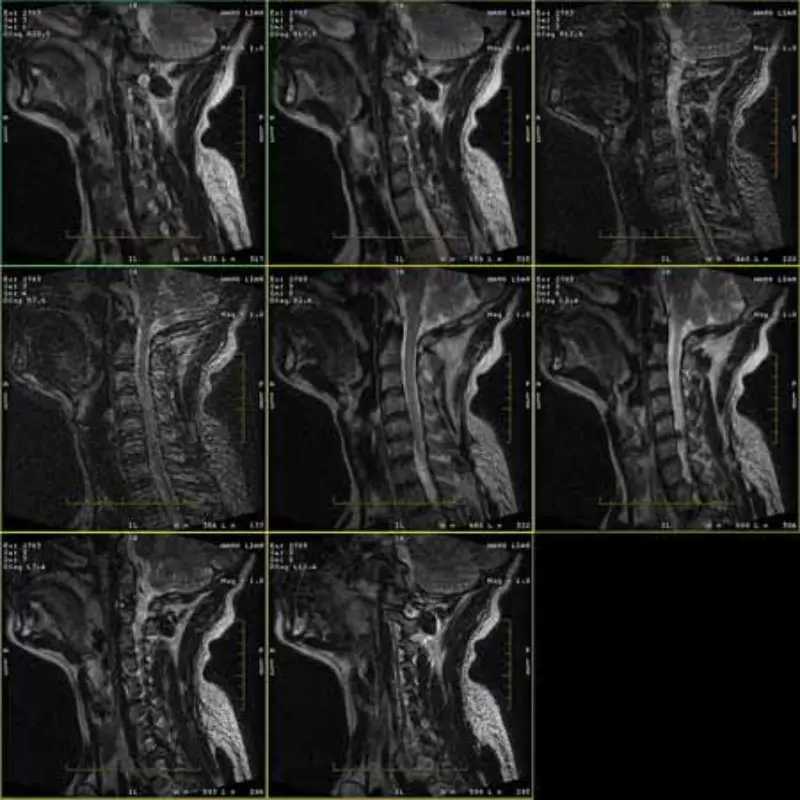

Οι εικόνες των πρωτοκόλλων FRFSE και GRE έχουν φάντασμα και μερικές φορές εικόνες χαμηλού SNR εμφανίζονται σε μία σειρά. Αλλά οι εικόνες πρωτοκόλλου SE είναι φυσιολογικές.

Παρακαλώ δείτε επισυνάψτε εικόνες.